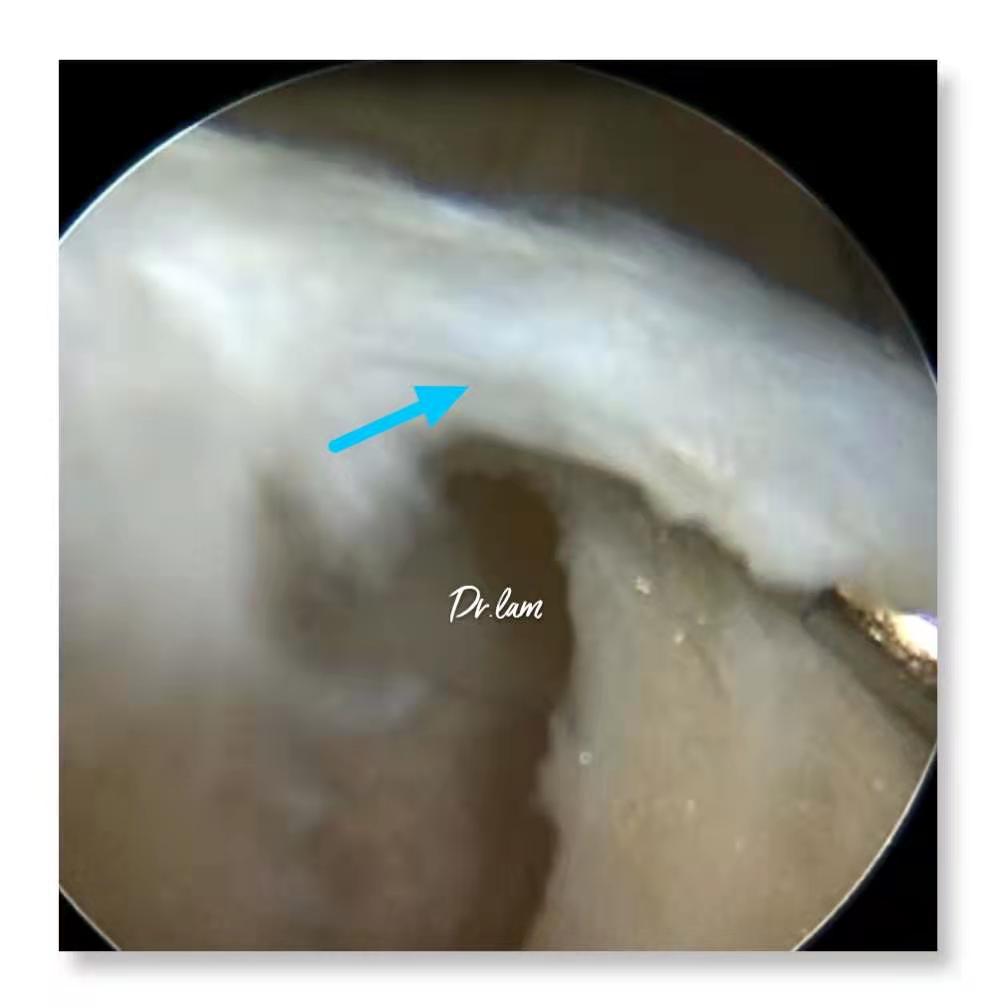

最后,我们再一起看看几张图片,加深了解这个容易被忽视的疾病。

关节镜下轻度病变的髌内侧滑膜皱襞